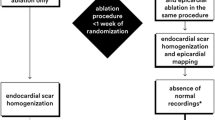

In a single-center prospective study of 11 patients with ARVC-related VA, Berruezo et al. reported that in addition to an endocardial and/or epicardial approach for ablation of the clinical ARVC VT, complete scar dechanneling with elimination of either endocardial and/or epicardial scar-conducting channels (i.e., intrascar, interscar, or between scar and valvular annuli) is a promising approach to improve long-term success rate of CA [31••]. In fact, the combined endocardial and epicardial VT ablation eliminated all clinical and induced VTs, and the addition of scar dechanneling resulted in non-inducibility in all cases, significantly improved from earlier studies. Seven patients continued on sotalol. During a median follow-up of 11 months, only one patient (9%) had a VT recurrence. To identify these channels, an endocardial high-density substrate voltage map of the RV was obtained during stable sinus rhythm using the CARTO system. Image integration between a preacquired contrast-enhanced cardiac CT or contrast-enhanced CMRI was performed using CartoMerge software. Substrate mapping was performed to identify scar and conducting channels (CCs) inside the scar, between the scars, or between a scar and the tricuspid annulus. The CCs have been defined as pathways of orthodromically activated sites inside the scar. Scar CCs were identified by (1) a color-coded voltage map adjustment of the lower and upper thresholds (voltage channels) and (2) the presence of >2 tagged recordings of electrograms with a duration >70 ms and/or isolated, delayed components (E-IDCs), with the delayed component showing sequential orthodromic activation (late potential channels) (Fig. 4). Those CCs between two confluent scar areas or between a scar and the tricuspid annulus were considered in addition to intrascar CCs. After CC identification, the entrance of each CC in the scar was tagged during sinus rhythm. The CC entrance was defined as the E-IDC with the shortest delay between the far-field component of healthy muscle (usually low frequency, high voltage) and the local component (delayed activation, usually with fractionation and low voltage) corresponding to the activation of myocardial tissue in the scar.

Epicardial substrate voltage map of a patient with familial ARVC and VT storm. A wide inferolateral and apical dense scar was identified. A conducting channel (CC) was identified at the base of the scar by tagging the E-IDCs (blue dots) but not with a voltage adjustment. Electrograms on the left correspond to the CC at the right ventricular outflow tract (blue dots). The entrance of this CC during sinus rhythm was identified on the basis of the activation time of the delayed components of the E-IDCs. The activation sequence was from inferior to superior, as shown on the sequential electrogram activation time measurement (M1–M2). In this case, voltage mapping was also able to show this CC. Two additional rows of tagged E-IDCs identified two CCs parallel to the tricuspid annulus, with an activation sequence from superior to inferior. RF applications at the CC entrance eliminated both channels with a low number of applications. In this patient, both intrascar and interscar CCs (due to the presence of confluent patchy scars) were eliminated. With permission from Berruezo et al. Circ Arrhythm Electrophysiol. 2012;5:111–21 [31••]

The initial step was RF catheter ablation of the clinical VT. Activation mapping and entrainment mapping were used for sustained, well-tolerated VT, and substrate-based ablation guided by pace mapping was used for non-sustained or non-tolerated VT. In addition to the clinical VT ablation, elimination of all CCs identified during substrate mapping was attempted by means of combined endocardial and epicardial scar dechanneling. It has been reported that the higher the scar heterogeneity in patients with ischemia is, the higher the arrhythmogenic potential of scars is. Scar heterogeneity can be recognized during substrate voltage mapping and permits identifying CCs of consecutive electrograms with higher voltage amplitude than the surrounding area, which have been demonstrated to be responsible for VT reentrant circuits; their elimination renders VTs non-inducible. Therefore, to reduce possible VT relapses using different CCs than those participating in the clinical VT, the substrate-based ablation strategy employed endocardial and epicardial scar CC elimination on top of clinical VT ablation (Fig. 5) [31••]. The same group a few years later published a second study, which confirmed that the scar and the CCs responsible for VTs in patients with ARVC are mostly epicardial and have a typical distribution, with a preferential location in the subtricuspid area. The CCs can be identified during substrate mapping in SR by using both techniques: bipolar voltage adjustment of the upper and lower thresholds and tagging the E-IDCs with sequential activation inside the scar. However, the latter should always be used for a substrate-guided ablation, as this technique identifies a higher proportion of CCs and, more importantly, most CCs that serve as the substrate for VTs. Using only the bipolar voltage adjustment, more than 70% of the CCs and 60% of the VT isthmuses would not be identified [32].

Epicardial substrate voltage map with CCs identified by tagging electrograms with isolated, delayed components. CC entrance is marked with black dots. The amplitude of the far-field component decreases and the delay of the local component of the electrogram registered at the border zone increases with the distance from the edge of the scar. b 3D anatomic map with red dots at locations where radiofrequency was delivered (mainly at the CC entrance). c A new map after radiofrequency ablation was obtained. Of note, a few applications eliminated all isolated, delayed components and increased the epicardial scar area. d RV electrogram registry from the distal dipole of the ablation catheter and electrogram registered at the proximal dipole of the ablation catheter during radiofrequency application in a CC entrance in this patient. The electrogram has two components. The first represents the far field of the normal myocardium, and the second (black arrows) represents the local activation at the CC entrance. During radiofrequency application, a delay precedes the CC entrance block (asterisk). With permission from Berruezo et al. Circ Arrhythm Electrophysiol. 2012;5:111–21 [31••]